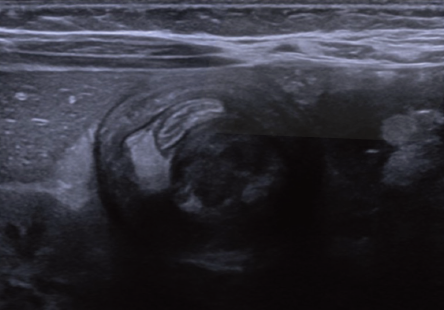

1. Se realizó una ecografía abdominal urgente que incluyó imágenes ecográficas transversales y longitudinales (figuras 1 y 2). ¿Cuál es el diagnóstico más probable?

Figura 1 Ultrasonido abdominal del flanco derecho en plano transversal.

Figura 2 Ultrasonido abdominal del flanco derecho en plano longitudinal

3. ¿Qué signo puede identificarse en las imágenes obtenidas por ultrasonido en plano longitudinal?

2. Signo del pseudoriñón